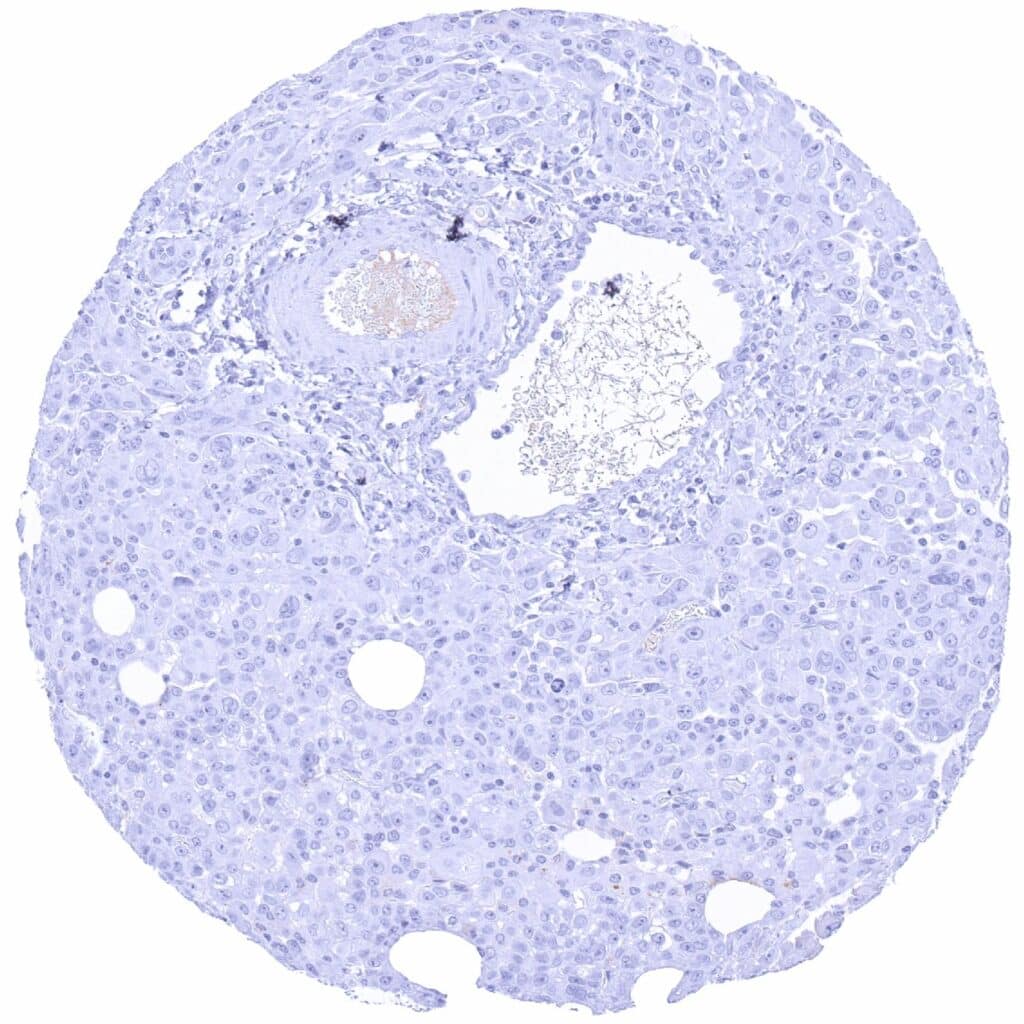

Liver – PAX6 negative hepatocellular carcinoma